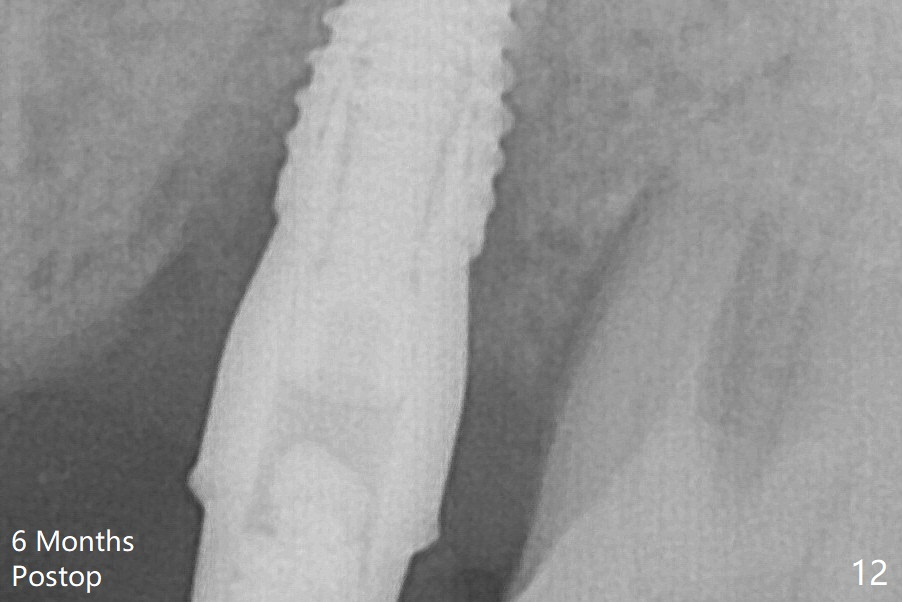

Bone density between #13 and 14 appears to increase 3 months postop (Fig.10).  There seems to be more bone growth (i.e., decreasing gap) 6 months postop (Fig.12).